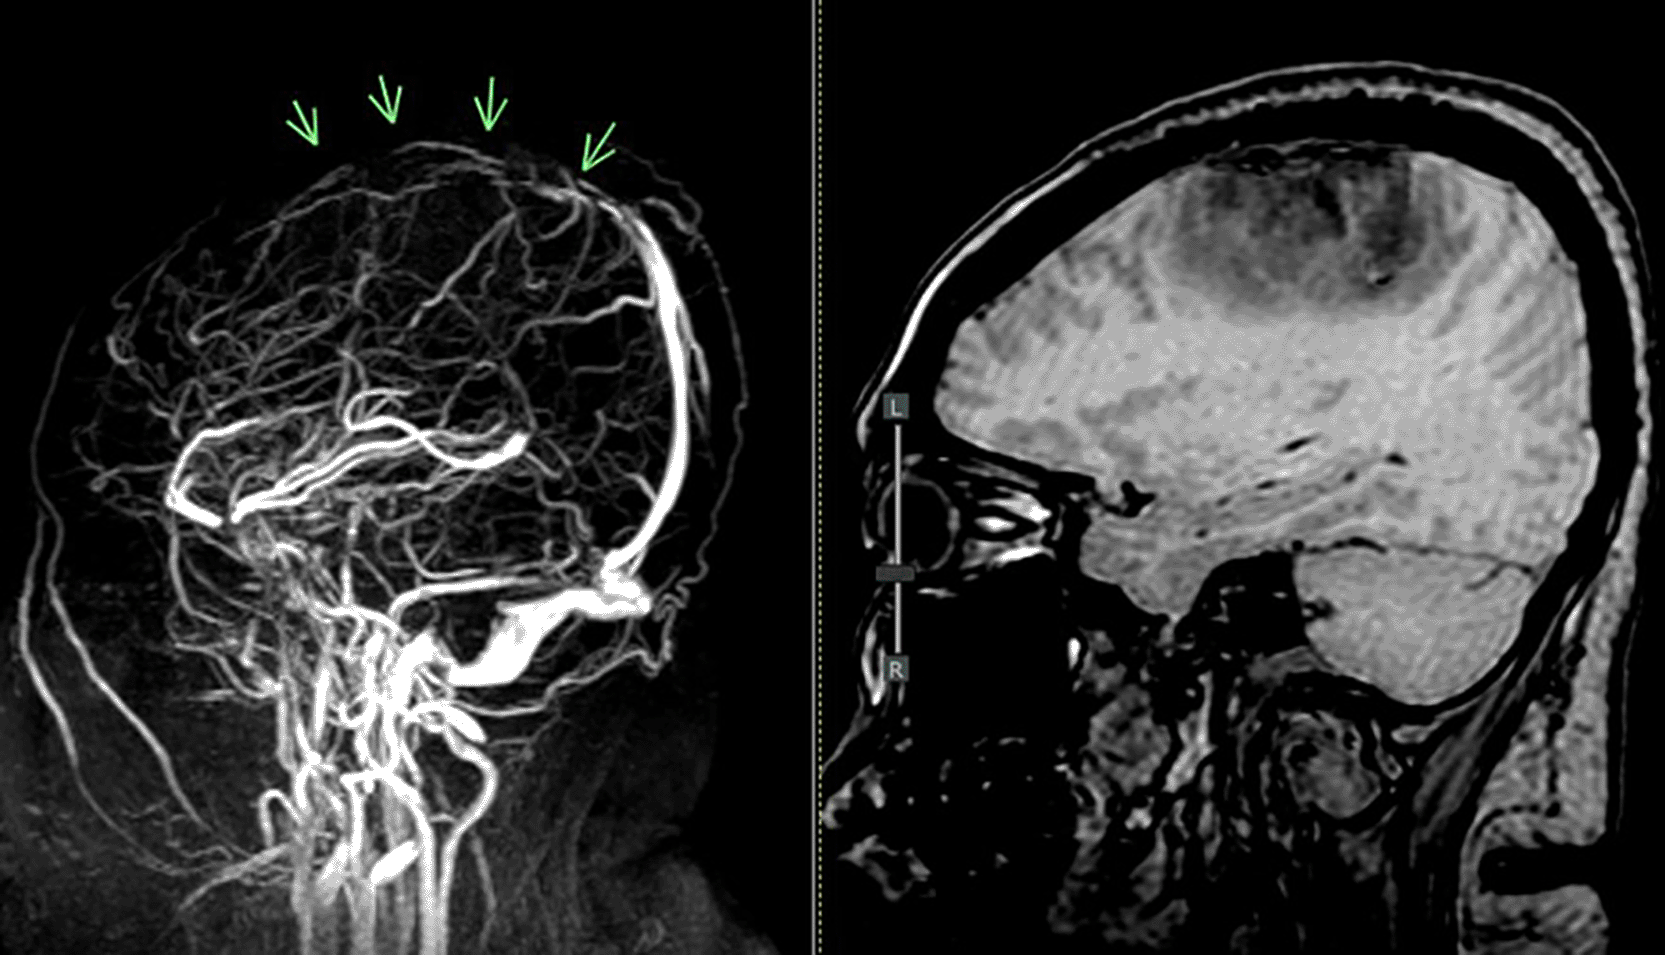

The patient in the ICU remained conscious (E4V5M6) but experienced another seizure. Therapy was administered as a loading dose of mannitol at 1 g/kg body weight, followed by a maintenance dose of 0.5 mg/kg four times daily, continuous magnesium sulfate at 2-3 mg/kg/hour, citicoline at 500 mg three times daily, and sedation with dexmedetomidine at 0.5-0.7 mcg/kg/hour. The patient exhibited clinical and hemodynamic enhancement. On the subsequent day (ICU H-3), the patient reiterated complaints of intense headache and agitation (E3V5M6), which were succeeded by seizures and diminished consciousness. A neurological assessment revealed left hemiparesis, with right/left motor strength recorded at 5-5/4-4, and no nuchal rigidity was observed. A CT scan of the head revealed a “Dens sign” alongside intracranial hemorrhage (ICH) encircled by considerable edema in the superior sagittal sinus region, accompanied by subarachnoid hemorrhage. Nimodipine at a dosage of 6x60 mg and a hypertonic saline loading dose of 3 mg/kg, subsequently followed by 1 mg/kg body weight every 8 hours, were administered. The left side limbs exhibited a decline in strength to 5-5/2-2, accompanied by diminished motor function in the right side limbs (4-4/2-2). The CT scan of the head without contrast (NCCT, Figure 1) prompted a consultation with the neurology division, followed by a D-dimer test yielding a result of 4870 ng/ml. An MRI and MRV of the head revealed a hemorrhagic venous infarct in the right-left parietal lobe (dominant right, volume approximately 15.5 cm), accompanied by perifocal edema that displaced the right-left lateral ventricle inferiorly, resulting in subfalcine herniation to the left side due to thrombosis with anteromedial occlusion of the superior sagittal sinus ( Figures 2-3). Anticoagulant therapy commences with an initial dose of 5000 IU of low molecular weight heparin (LMWH), followed by a maintenance dose of 1.8 IU/kg body weight, and a consultation with the neurosurgery division for decompression craniectomy.

MRV = magnetic resonance venogram.

Our patient presented with diffuse acute headache, positional worsening, bilateral motor deficits, and thrombosis in the SSS with bifrontal hemorrhagic infarction, edema, and subcortical damage—confirmed via CT and MRI-MRV ( Figure 4). Her symptoms, lasting over one month, reflect rare prolonged ICP elevation and venous congestion.